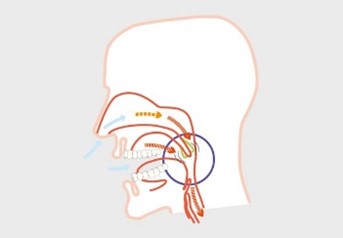

Silensor se sastoji od jedne zubne udlage za gornju čeljust i jedne zubne udlage za donju čeljust. Donja čeljust se zadržava u prednjem položaju (protruzija) s dvije spojnice koje su fiksirane bočno na udlagama. Na taj način silensor sprječava približavanje stijenki mekih tkiva. Sa silensor udlagom pokreti donje čeljusti su mogući lijevo-desno i naprijed bez povlačenja unatrag.

Zbog ove funkcije silensor je istodobno učinkovit i udoban. Klinički testovi su pokazali da potiskivanje donje čeljusti prema naprijed značajno smanjuje hrkanje za kod više od 90% pacijenata i može smanjiti indeks apneje za 50%